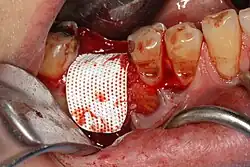

Socket filled with bone, membrane secure on the tongue side

Barrier membrane covering the bone